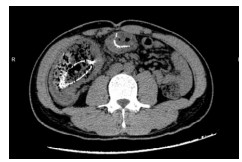

1 资料与方法病例1,患者女,72岁,2020年9月2日因“腹痛3 d”来本院急诊,拟“升结肠肿瘤伴肠梗阻”收住院。半月前因“胆囊结石”在当地医院行腹腔镜下胆囊切除术。本次入院查体:腹部膨隆,右下腹部压痛明显,轻度反跳痛。WBC13.3×109/L, N 84.0%。腹部增强CT提示升结肠管壁不规则增厚伴管腔狭窄,回盲部及远端回肠扩张明显(图 1)。肠镜检查:升结肠肿物,予取病理活检后,在肠道狭窄处行肠梗阻金属支架植入解除梗阻(以维持肠腔的通畅性和减少肠道毒素的进一步吸收)。肠镜病理提示:(升结肠)管状绒毛状腺瘤,部分高级别上皮内瘤变。3 d后复查腹部平扫CT示回盲部及远端回肠原先扩张的肠腔已明显缩小(图 2)。因患者既往有糖尿病史,时常合并胸闷胸痛,心电图示侧壁T波直立,心内科会诊建议行心脏冠脉造影。冠脉造影提示心脏左前降支中段狭窄约百分之八十,远端约百分之九十狭窄。经多学科讨论后认为患者目前急性肠梗阻症状已经缓解,建议可先予冠状动脉药物涂层支架植入术,再予以替格瑞洛口服抗凝治疗,1个月后再次入院行结肠肿瘤手术。患者于2020年10月9日再次入院行腹腔镜下右半结肠癌根治手术,手术过程顺利。术后病理报告:(升结肠)高-中分化腺癌,T3N1M0。患者术后13 d出院,并接受了后续的规律化疗。目前患者恢复良好。

| 图 1 腹部增强CT示回盲部及远端回肠扩张明显、肠腔充满肠道内容物 |